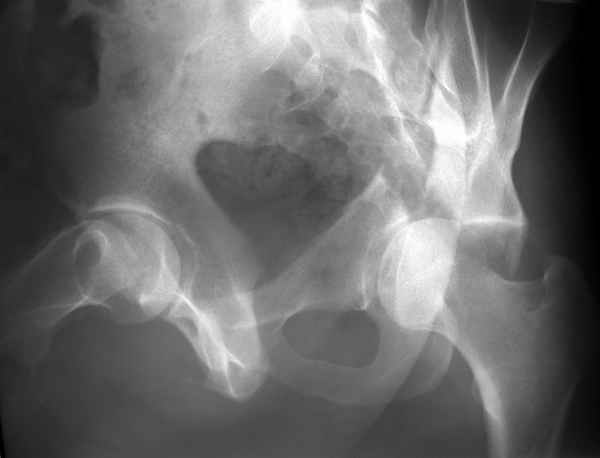

Повреждение сложное. DS:Ротационно нестабильное повреждение таза, перелом боковой массы крестца,ипсилатеральный высокий двухколонный перелом вертлужной впадины с центральным смещением сустава, двусторонний перелом лонных и седалищных костей.

Конечно изнутри таза массивная гиперпластическая мозоль - пришлось немного попотеть и интерпозиция по плоскости перелома. Хорошо был виден ствол нерва с внутренней стороны вырезки - сделали блокаду, как положено. После операции движения стопы в полном объеме чувствительных расстройств нет. Репозиция удалась - мы были в легкой эйфории - внесуставной доступ и т.д. Через сутки стопа повисла - грубых выпадений на ЭНМГ нет, но тем не менее ишемический неврит малоберцовой порции седалищного нерва - бич застарелых повреждений.

Ах если бы Русские люди не обманывали себя и больных, а направляли бы срочно в специализированные отделения, то можно было бы получить хороший результат куда меньшей кровью пациентов и сердечных ран хирургов. Посылаю еще два снимка. Привет ЛАФ.